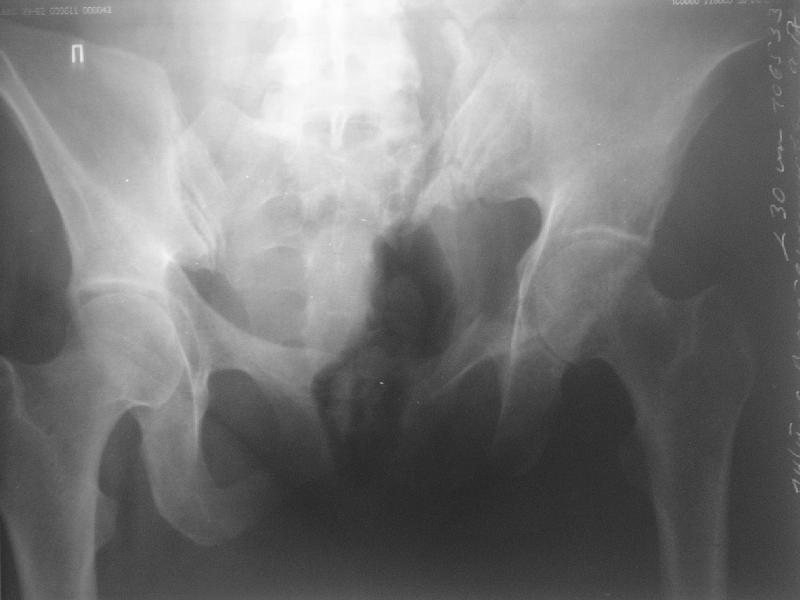

Прооперировали молодую девушку 32 лет спустя 9 мес после травмы. Имелся стойкий болевой синдром, неопороспособность левой н/конечности, моторные и сенсорные нарушения в левой голени и стопе, патологическая подвижность левой половины таза. Первым этапом закрыто в аппарате исправили деформацию ( в течении 2,5 нед). Вторым закрытое введение илиосакральных винтов в крестец (канюллированные 7,2 мм Chm) + туннелизация зоны псевдоартроза спицама Киршнера, реконструкция передних отделов таза, накостный остеосинтез . Аппарат частично демонтирпован, оставлена "передняя рама" После устранения деформации отмечен регресс неврологической симптоматики, уменьшение болевого синдрома. Интересующие вопросы: 1. Прогноз для сращения псевдоартроза крестца. 2. сроки нагрузки весом левой половины таза. Буду очень признателен за ваши мнения по этому поводу.A female 32 y.o. admitted to our unit 9 months after initial injury with pain, inability to bear weight at the left lower limb, sensor and motor disturbances in the left foot and tibia, with mobility of the left hemipelvis.At first closed reduction was performed by an external fixator within 2,5 weeks. After correction her pain decreased and some neurological progress was achieved. Now two iliosacral screws 7,2 mm were inserted, and anterior lesion was fixed by a plate. External fixator was partially unmounted, only anterior frame left in place.Images attached.How would you evaluate chances of healing of the sacrum with the current position?When would you allow weight-bearing of the left leg?THX in advance.

Примерно такой фиксатор наложил вчера ночью, но патология была экстренная травма: больному 53 года, поступил после мотоциклетной травмы, черепно-мозговой, абдоминальной, челюстно лицевой с потерей одного глаза, сосудистой и из скелета перелом крестца слева с диастазом симфиза и множественные переломы ребер.

Здесь соблюдался алгоритм больному с внутритазовым кроветечением после нестабильного перелома таза.

Одновременно с хирургами, которые занялись ксплоративной лапаротомией, мы приступили к фиксации временным аппаратом для уменьшения диастаза симфиза. После установки аппарата удалось стабилизировать давление, потом наше место занял сосудистый хирург, который нашел кровоточащую левую артерию epigastrica. Кровоточаший сосуд затромбизировал эндоваскулярно введением 4 coil placement.

Много кровепотери было из лицевых ран. Кроме забрюшинной гематомы, крови накопилось в абдоминальной части между мышечными стенками и под кожей. Кровопотерю заместили более 20 доз препаратов крови и INR опустился изначалнего 9.5 до 1.0 в конце. Находится в реанимации, стабильный, надеемся через несколько дней займемся окончательной фиксацией переломов костей таза.